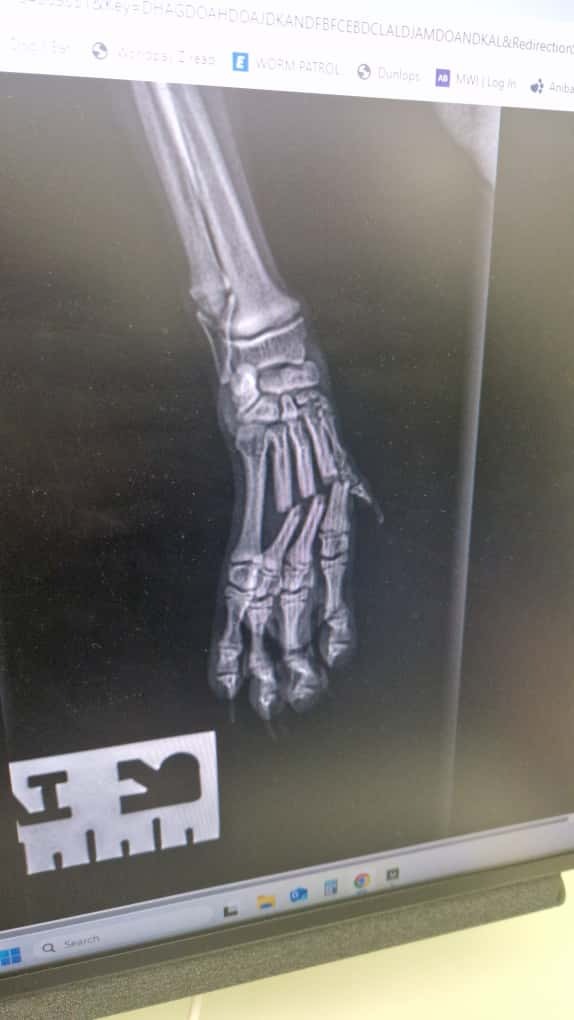

hi my name is Dean, i am setting up this page asking for help with my 15 week old puppy Pomchi who's name is snoopy need yesterday he was playing with his mum on the bed and accidently fell off and landed on his leg/paw braking three of his metacarpal's unfortunately i was complacent and didn't setup his pet insurance, i have been to a spoke with the vet and the best option for repair is a surgery that costs £2500 or the lesser option of £1500 splinting and aid in the hopes it will heal properly which i currently don't have and the vet does not give payment plan so i am ask for any and as much help as i can get.